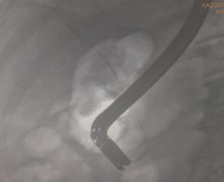

凭借扎实的ERCP专业功底和内镜操作技能,ERCP团队在短短20分钟就顺利完成了ERCP+EST+取石+ERBD+ENBD术,即胆总管造影、十二指肠乳头切开、胆总管末段嵌顿结石取出、胆总管支架植及鼻胆管引流术系列手术操作。

(ERCP术后胆管支架、鼻胆管X光线图片)

随着胆道梗阻的解除,胆道压力降低,患者病情逐渐好转。术后10分钟左右,患者血压就回升至90/60mmHg,烦躁不安症状明显好转,能清晰回答问题,同时体温也逐渐下降恢复至正常。